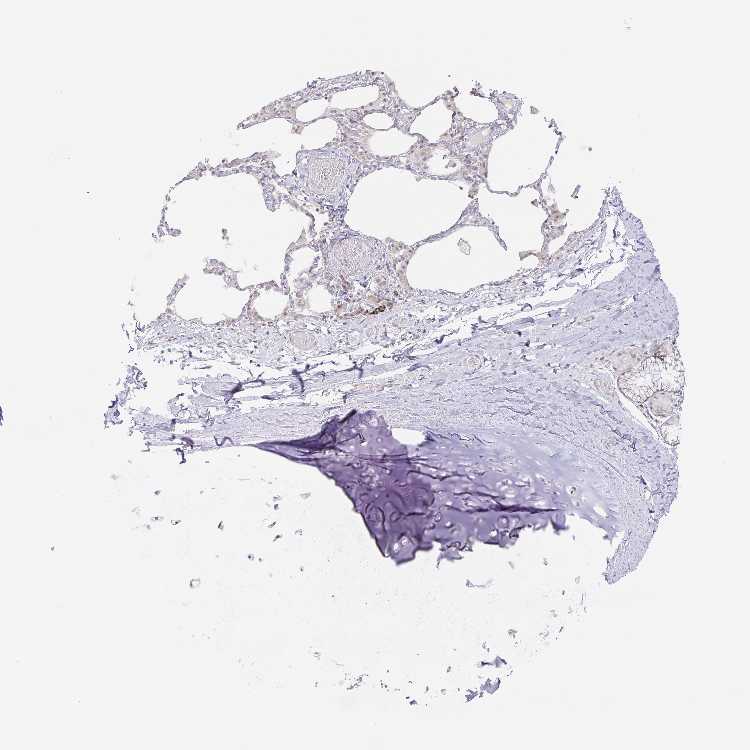

SOFT TISSUE 1 - Antibody stainingi

Antibody staining in the annotated cell types in the current human tissue is reported as not detected, low, medium, or high, based on conventional immunohistochemistry profiling in selected tissues. This score is based on the combination of the staining intensity and fraction of stained cells.

Each image is clickable and will lead to virtual microscopy that enables deeper exploration of all samples and also displays staining intensity scores, fraction scores and subcellular localization as well as patient and tissue information for each sample.

Antibody HPA019652

Chondrocytes Not detected

Fibroblasts Not detected

Peripheral nerve Not detected